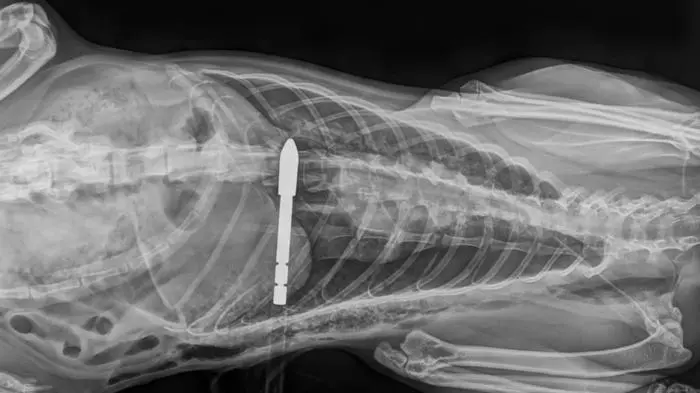

Tierquäler schoss in Zmuln bei Liebenfels mit Pfeil auf Katze

Eine freilaufende Katze wurde von einem Unbekannten mit einem Pfeil schwer verletzt. Das Tier wurde mit schweren Lungenverletzungen in eine Tierklinik gebracht. Dort kämpft sie um ihr Leben.

Das Röntgenbild zeigt die Verletzung